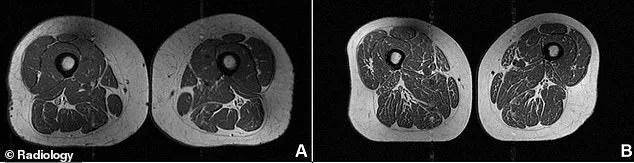

The contrast is stark when comparing MRI scans of two women of similar age and weight. One 61-year-old woman, whose diet contained 30 percent ultra-processed foods, shows minimal fat infiltration. In contrast, a 62-year-old woman, whose diet consisted of 87 percent ultra-processed foods, displays the devastating, marbled destruction of her muscle tissue.

White streaks of fat can replace healthy muscle, mirroring the marbling seen in a steak. New research indicates that a diet high in ultra-processed foods (UPFs) triggers this exact process within human thigh muscles, directly weakening the tissue.

The study, published in the journal Radiology, paired these scans with detailed yearly dietary questionnaires. This allowed researchers to pinpoint the exact percentage of daily calories coming from UPFs. The findings revealed a direct correlation: as UPF consumption increased, intramuscular fat levels rose accordingly. This pattern held across the hamstrings, quadriceps, and inner thighs, and the link appeared even more pronounced when researchers measured abdominal circumference instead of BMI.